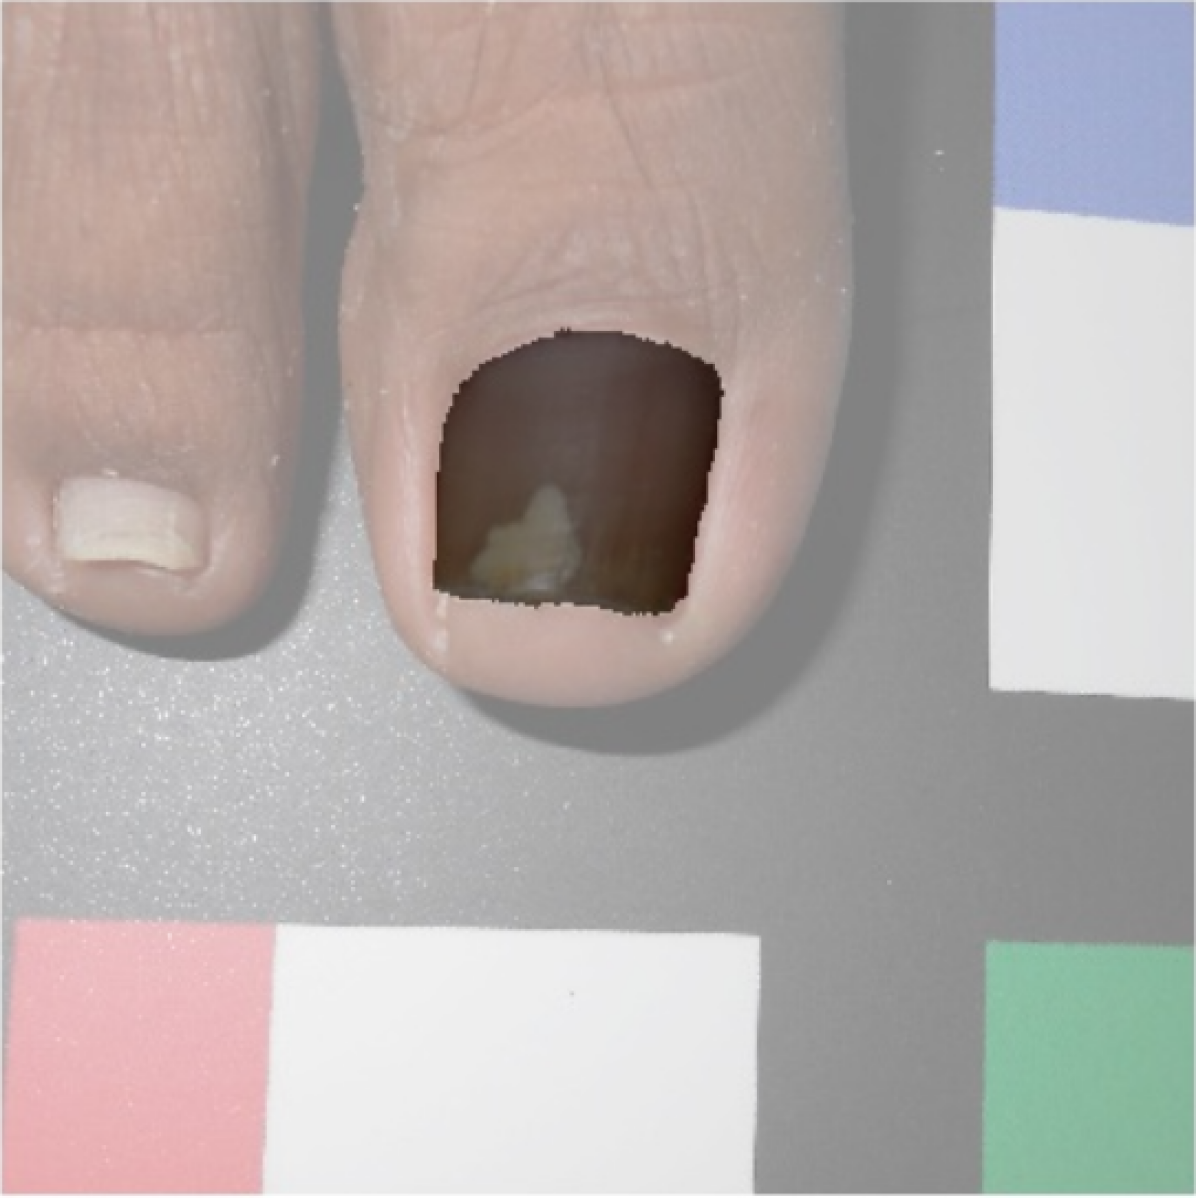

The dataset used in this study was taken in the clinical practice. Following the guidelines of a well-defined medical study, images were acquired in real conditions. All of them were captured in the doctor’s office with their smartphones’ embedded camera. To control some of the environmental conditions, we designed a template to use as the scene background (see Figure 2). During the acquisition process, however, we could not control some other environmental conditions, such as the capture viewpoint the camera setup or the illumination.

Before tackling the image segmentation problem, we perform an image normalization process based on the template’s known measures. It consists on transforming the input image, as seen in Fig. 3 (left), to an image with standard dimensions and orientation, Fig. 3 (right). To achieve our objective we detect the position of the template corners and geometrically transform the image with an affine mapping. As a result, all normalized images appear to had been taken under the same point of view. We remark that the three template colored squares are mapped to the top-right, bottom-right and bottom-left image corners. In particular, left foot images are mirrored. Normalized images are always set to measure pixels. Since the real region inside the template measures cm, a centimetre in the normalized image accounts for 300 pixels, which can be used to measure distances and areas.

The dataset is composed of 348 images of human big toes acquired using the doctor’s cameras attached to off-the-shelf smartphones. A sample image is found in Fig. 8. As previously explained, during the image acquisition stage, some parameters could not be controlled, such as the illumination, the specific capture viewpoint and the camera specifications.